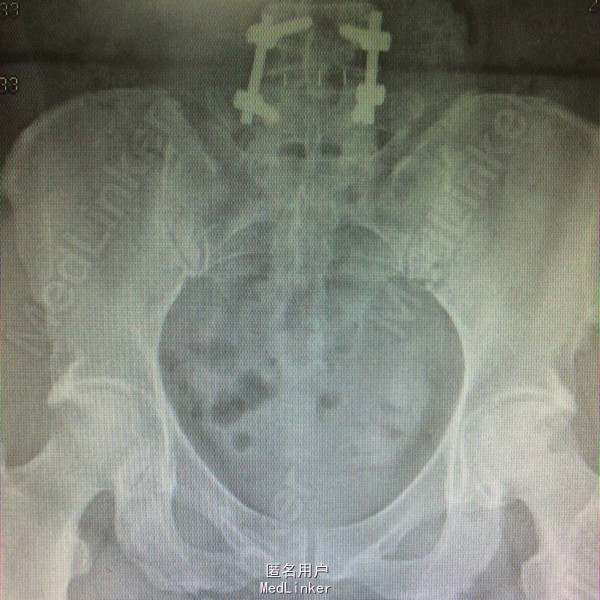

初步诊断:双侧股骨头缺血性坏死 鉴别诊断:X线片上未见骨肿瘤,骨囊肿等征象可与肿瘤相相鉴别,具体有待于进一步检查。 诊疗计划:1.卧床休息,暂不负重,对症支持处理。 2.完善相关检查(血、尿分析、肝肾功能、骨盆平片、髋关节CT、胸片ECG、心脏彩超等)。 3.择期手术治疗(髋关节置换术)。

左侧人工髋关节置换术 扶乖部分负重功能锻炼,不侧身,不盘腿,不直腿抬高。不深蹲 ,指导下功能锻炼促进肢体功能恢复,避免僵硬,继续预防血栓治疗。